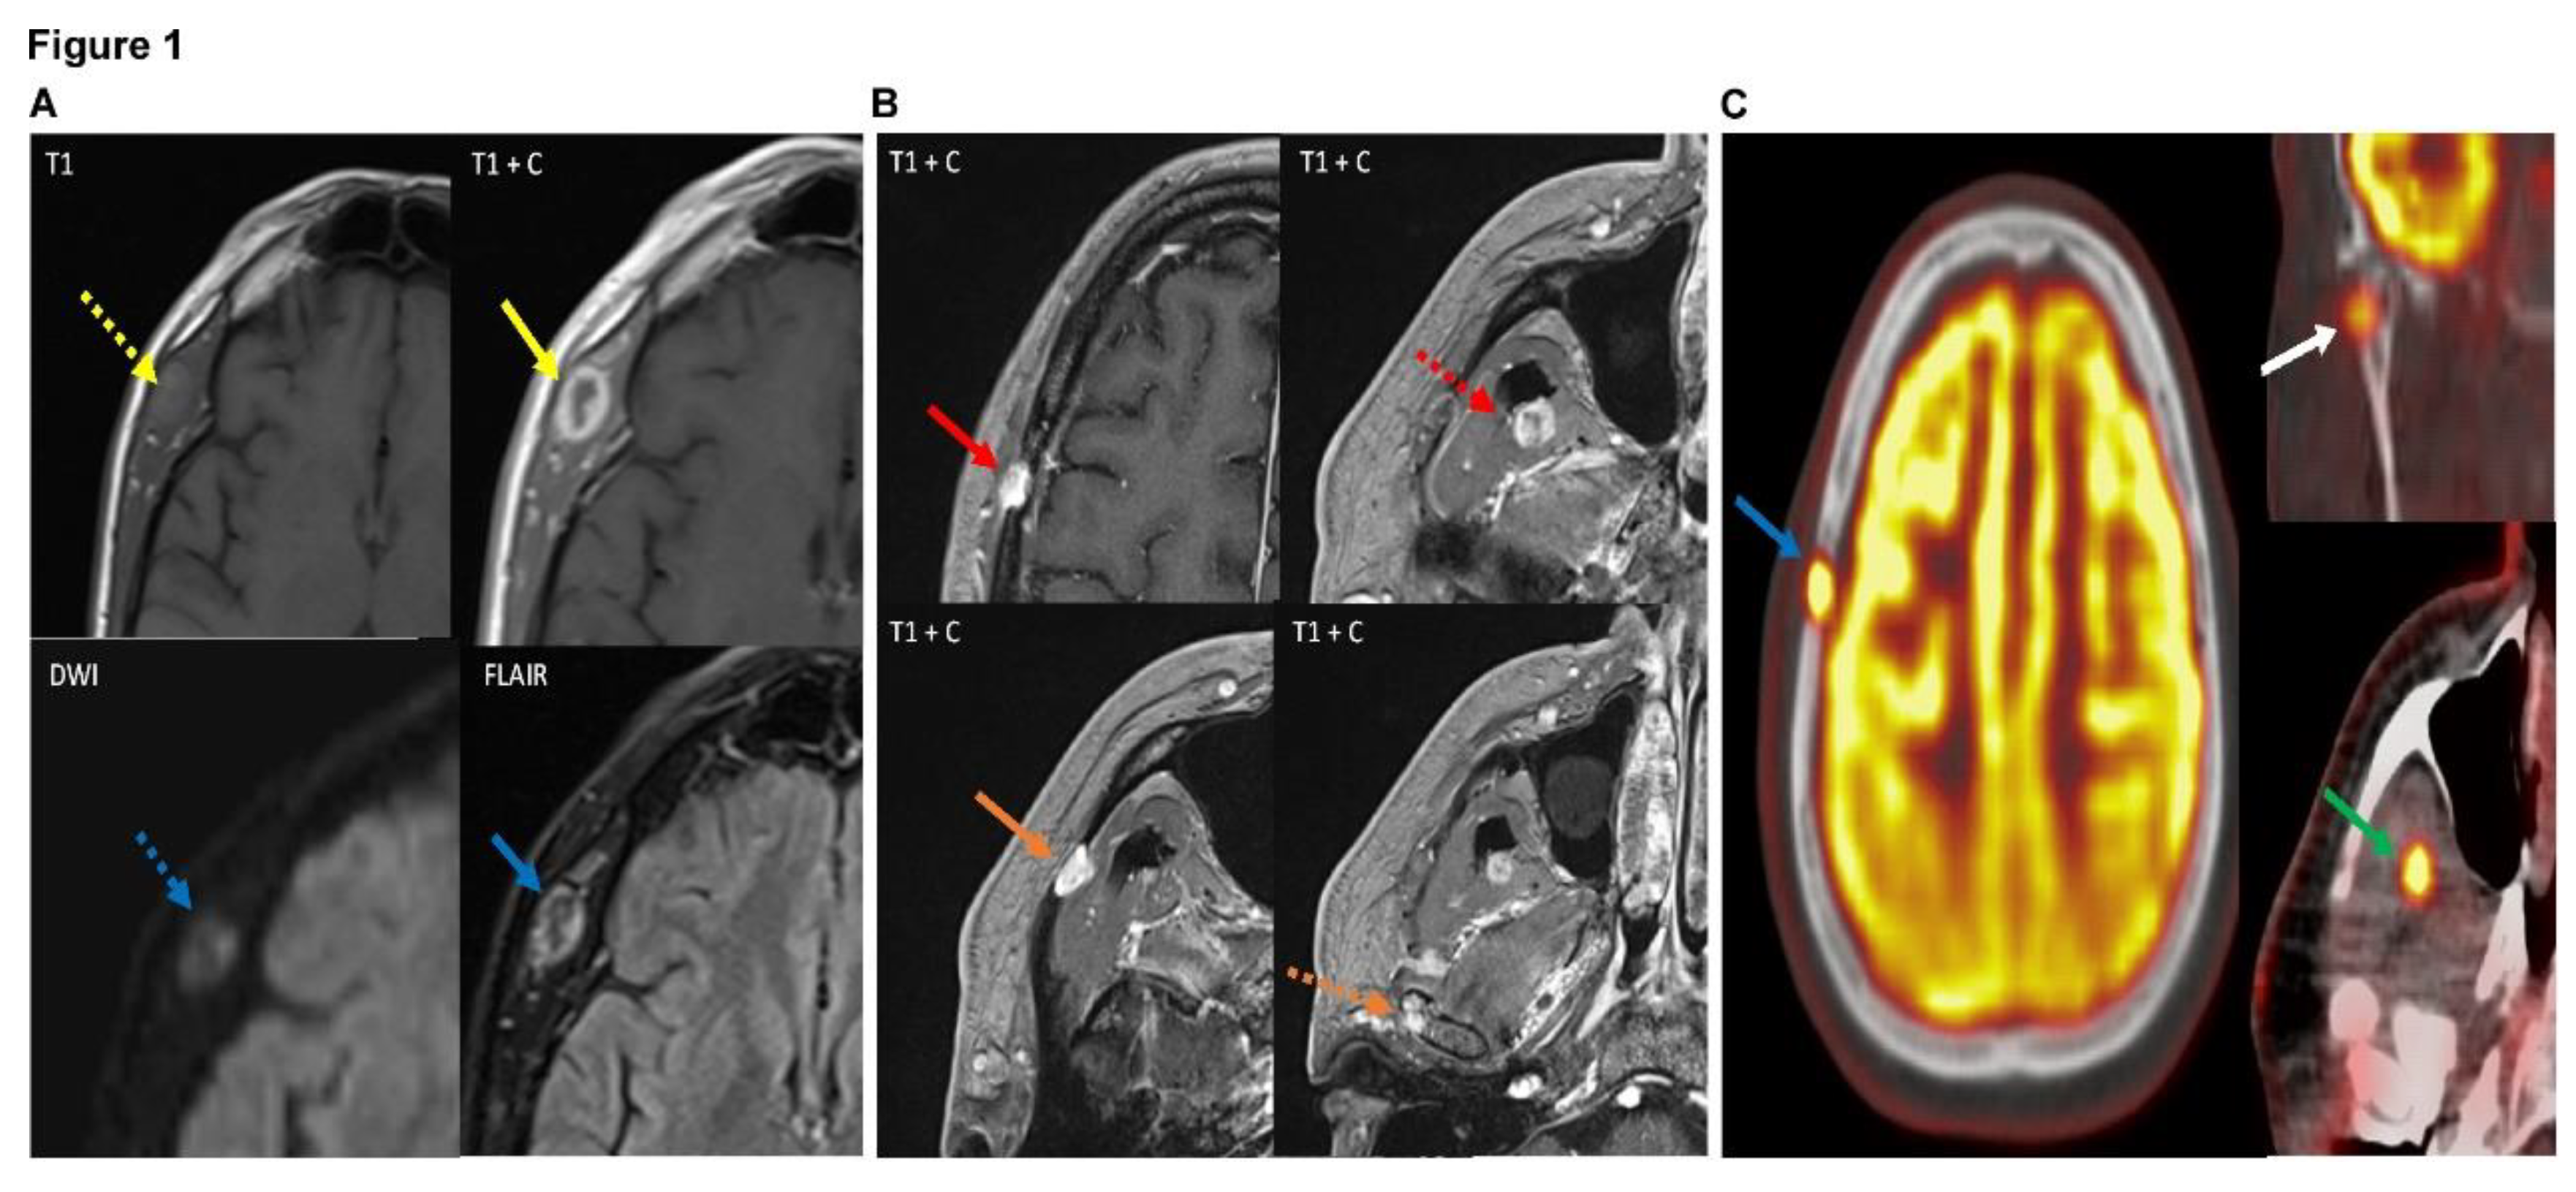

A 59-year-old male presented to the NeuroSurgery Clinic of University of California Irvine Medical Center on 3/31/2023 with a right temporal mass. About 6 months ago he did complain of pain in the right jay when he opened his mouth of yawned, and noticed the painless lump about 2 months ago. Subsequent MRI imaging showed a heterogeneous lesion measuring 1.6 x 1.1 cm centered in the right temporalis muscle (

Figure 1A). Furthermore, additional smaller 9 x 7 mm lesion within the right frontoparietal calvarium, 9 mm lesion within the right pterygoid muscles, and multiple small foci of signal abnormality within the right mandible (

Figure 1B). PET CT showed increased uptake in these lesions concerning for neoplasm (

Figure 1C). Laboratory values and past medical history was unremarkable except for hypertension, type II diabetes mellitus, hypercholesterolemia and arthritis. Past surgery history included endoscopic bilateral knee surgery and abdominal hernia surgery. No smoking, alcohol use or known allergy history. The patient eventually underwent a punch biopsy of right temporal mass.

(A) Axial images of the patient's MRI with and without contrast demonstrate a heterogeneous, peripherally enhancing 1.8 x 1.2 x 2.1 cm (AP x ML x CC) lesion centered within the right temporalis muscle (solid yellow arrow). The lesion demonstrates T1 isointensity to surrounding muscle tissue (dotted yellow arrow). On diffusion weighted sequences, the lesion demonstrates heterogeneous hyperintensity on diffusion restriction sequence (dotted blue arrow), suggesting areas of high cellularity of the lesion. FLAIR (fluid-attenuated inversion recovery) sequences also demonstrate heterogeneously increased signal of the lesion (solid blue arrow). Findings are suggestive of a neoplastic process, with possible cystic change or central necrosis due to the lack of central enhancement. (B) Multiple axial images of the patient's brain MRI (all T1 post-contrast enhanced sequences) demonstrate additional lesions with similar imaging features as the right temporalis muscle lesion in figure 1, including T2/FLAIR (fluid-attenuated inversion recovery) hyperintensity, diffusion restriction, and enhancement. Of note, these lesions demonstrate slight differences in enhancement pattern compared to the right temporalis muscle lesion, with more homogeneous enhancement compared to the right temporalis muscle which demonstrated more heterogeneous and peripheral enhancement. These additional lesions are centered in the right frontoparietal calvarium (red solid arrow), right lateral pterygoid/temporalis muscle (dotted red arrow), superficial aspect of the right masseter muscle with possible extension into the right zygomatic arch (solid orange arrow), and the right mandibular condyle (dotted orange arrow). These lesions were also avid on subsequent PET-CT (shown in figure 3), with the exception of the masseter/zygomatic arch lesion which demonstrated FDG uptake slightly above background activity at approximately 2.7 SUV. (C) PET-CT (positron emission tomography computed tomography) scan in the same patient demonstrates increased FDG (fluorodeoxyglucose 18F) radiotracer uptake with maximal uptake of 9.3 SUV in the right frontoparietal calvarial lesion which corresponds to a lytic lesion on the accompanying CT (blue arrow), concerning for neoplasm. There are additional FDG avid lesions in the right mandibular condyle with maximal uptake of 5.1 SUV (white arrow) and in the right temporalis/ lateral pterygoid muscle with maximal uptake of 8.7 SUV (green arrow), also concerning for neoplastic process. Previously noted right temporal lesion is not seen on this PET-CT as it was excised, although was shown to be FDG avid on prior PET (not shown).